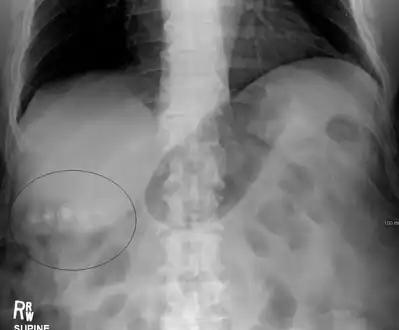

Gallstones typically form in the gallbladder and may result in symptoms if they block the biliary system.

Mixed (brown pigment stones) typically contain 20–80% cholesterol (or 30–70%, according to the Japanese classification system).[36] Other common constituents are calcium carbonate, palmitate phosphate, bilirubin and other bile pigments (calcium bilirubinate, calcium palmitate and calcium stearate). Because of their calcium content, they are often radiographically visible. They typically arise secondary to infection of the biliary tract which results in the release of β-glucuronidase (by injured hepatocytes and bacteria) which hydrolyzes bilirubin glucuronides and increases the amount of unconjugated bilirubin in bile. Between 4% and 20% of stones are mixed.[3]